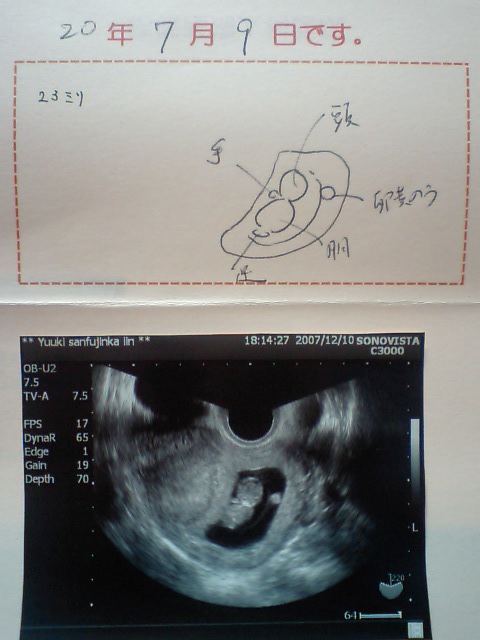

2008年7月9日 が予定日です

そして今回の写真~

←先生のイラスト

←大きさ23ミリ

(一週間で6ミリの成長です)

心臓バクバク動いてました